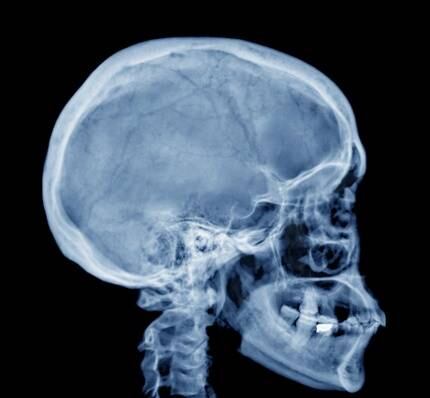

Según informó la citada casa de estudios, los expertos hallaron que esta protuberancia (que también fue llamada «pico» de hueso) se encuentra encima del cuello en la base del cráneo.

En términos más específicos, la «protuberancia occipital externa» es de un tamaño tan notorio que es fácilmente palpable al presionar dicha zona con los dedos.

El estudio determinó que al menos el 41% de los individuos analizados tenían este «pico» de hueso en la base del cráneo, teniendo en promedio un tamaño superior a los 20 milímetros. Incluso, el mayor era de 35,7 milímetros.